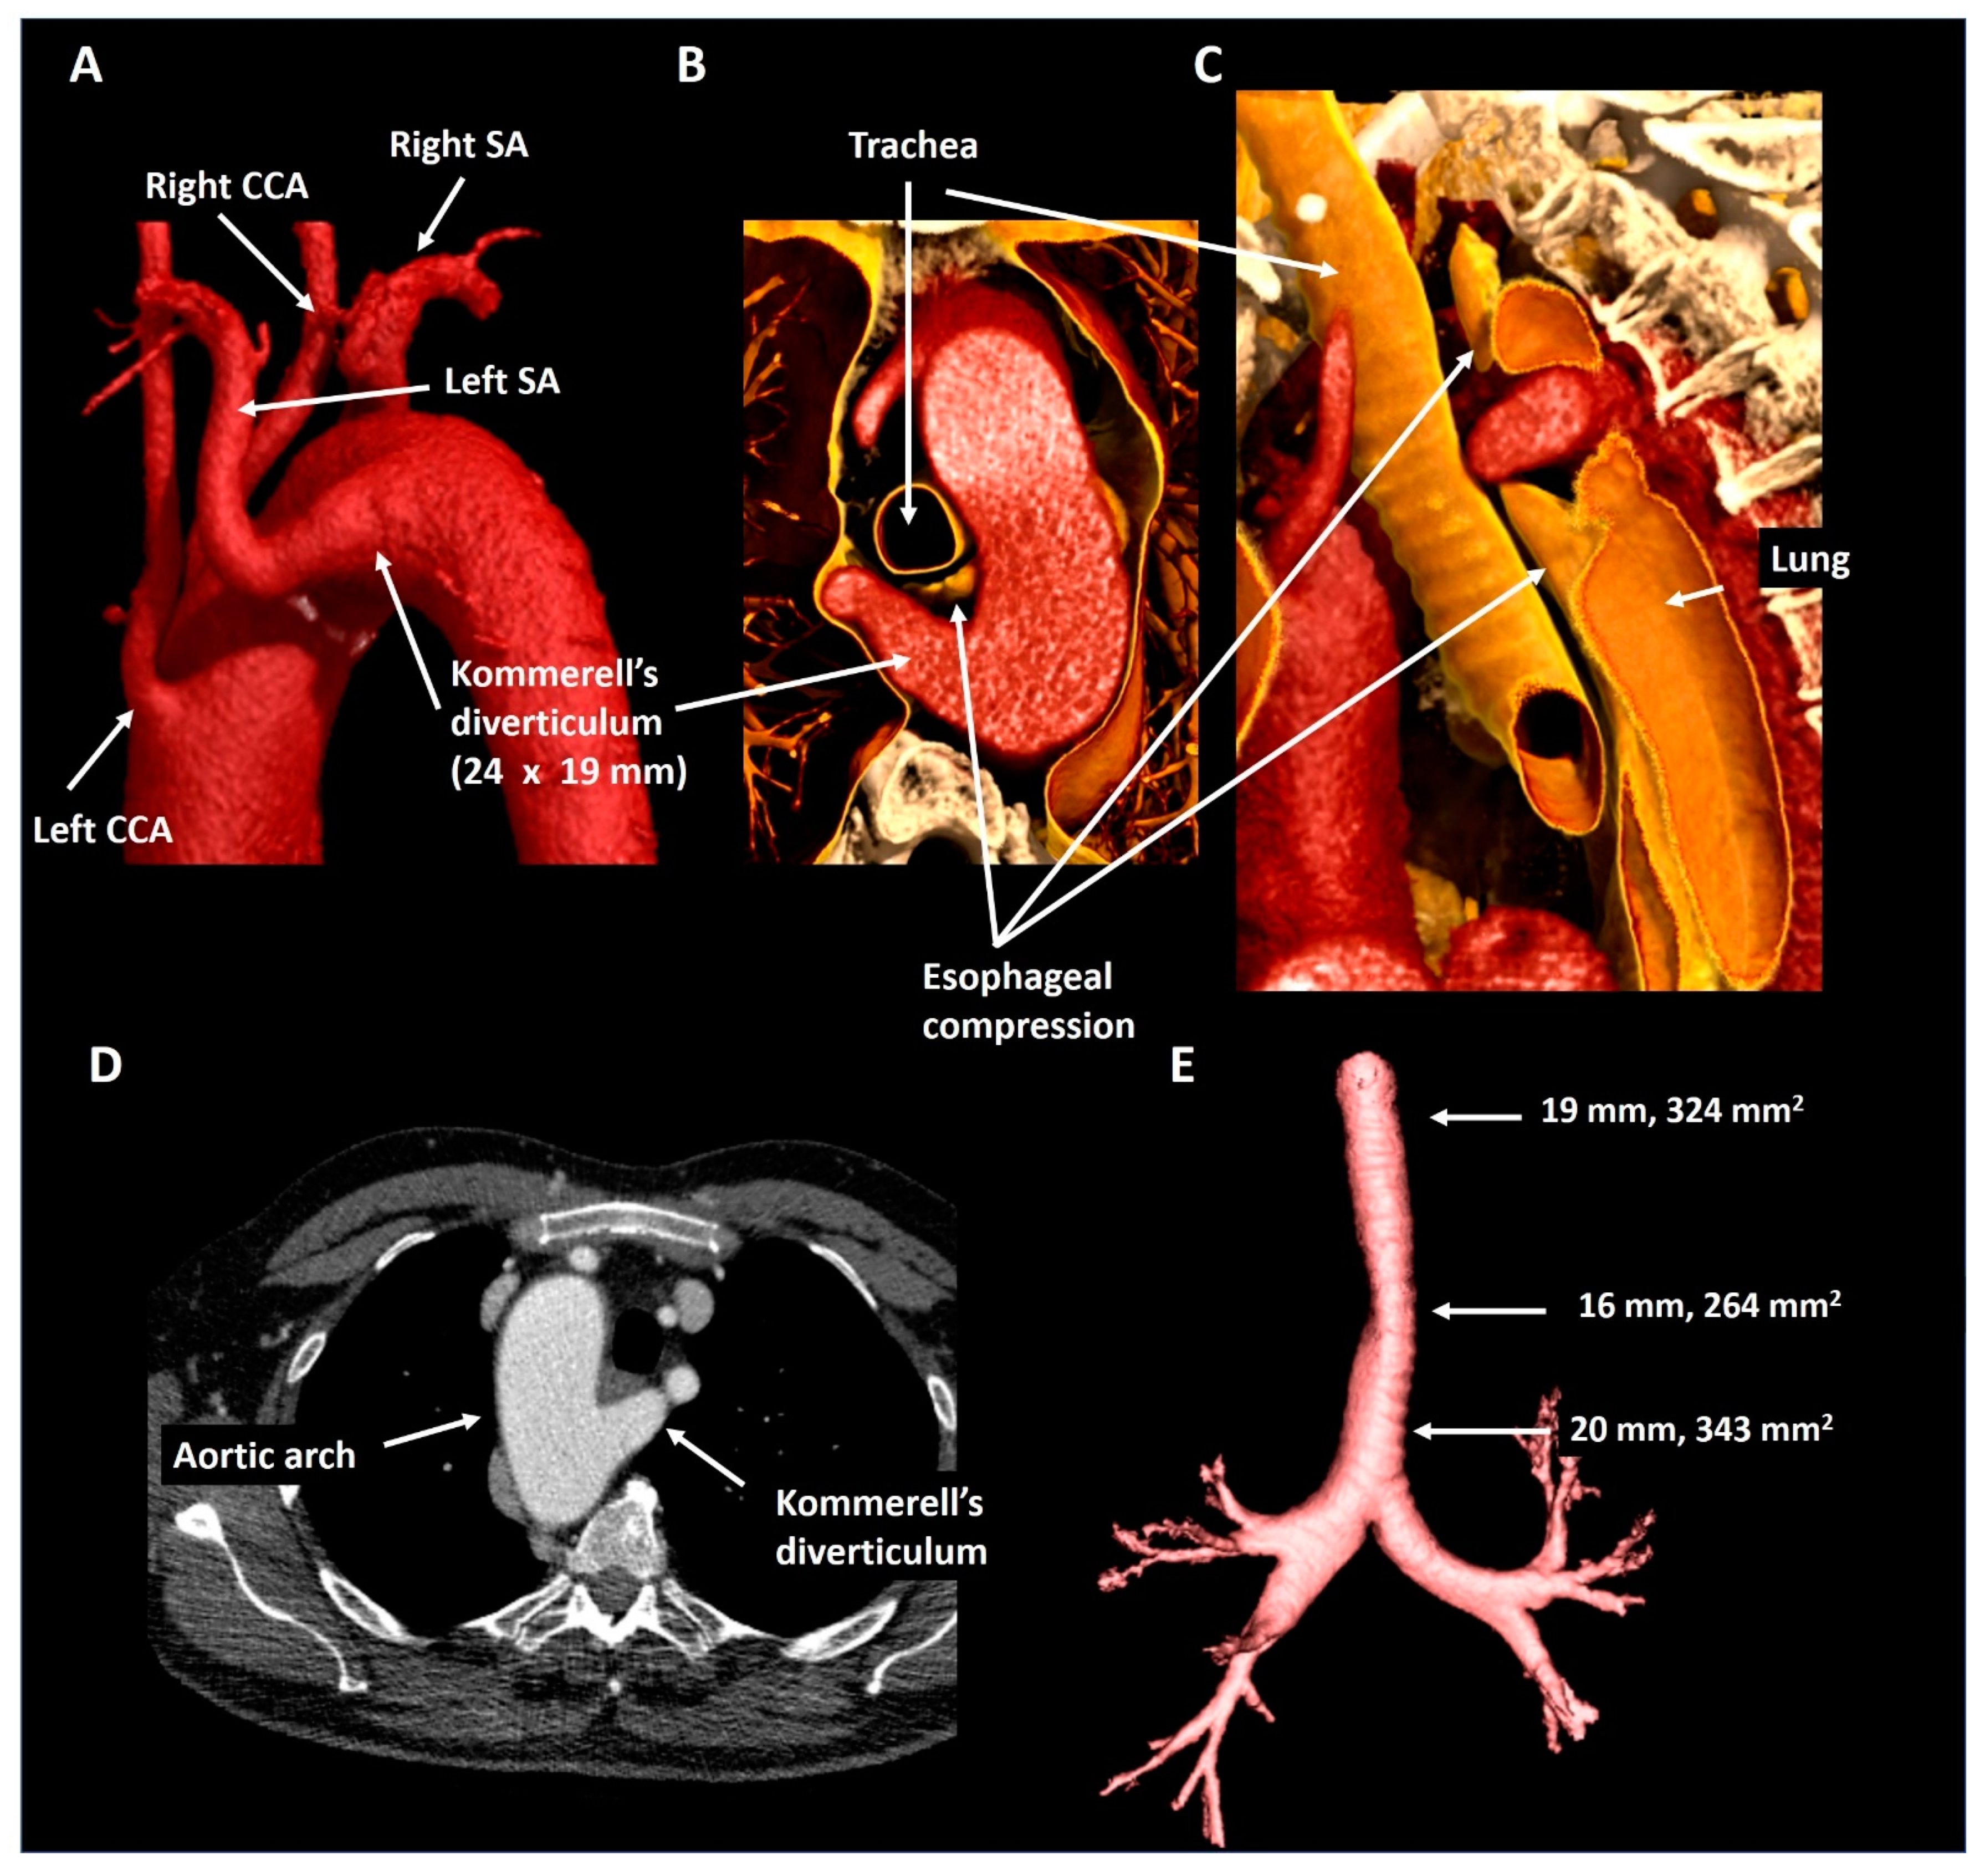

2.5. Patient 5

| Patient 5 | 63 | Male | Right-sided arch, aberrant LSA and KD | Asymptomatic esophageal compression | 24 × 19 mm, 343 mm2 | Incidental finding | Structural imaging follow-up |